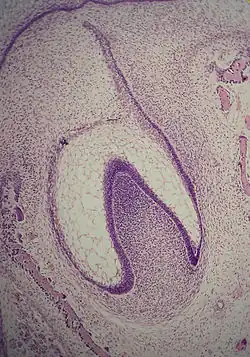

A: enamel organ

B: dental papilla

C: dental follicle

The tooth germ is an aggregation of cells that eventually forms a tooth.[2] These cells are derived from the ectoderm of the first pharyngeal arch and the ectomesenchyme of the neural crest.[1][3][4] The tooth germ is organized into three parts: the enamel organ, the dental papilla and the dental sac or follicle.

The first signs of an arrangement of cells in the tooth bud occur in the cap stage. A small group of ectomesenchymal cells stops producing extracellular substances, which results in an aggregation of these cells called the dental papilla. At this point, the tooth bud grows around the ectomesenchymal aggregation, taking on the appearance of a cap, and becomes the enamel (or dental) organ covering the dental papilla. A condensation of ectomesenchymal cells called the dental sac or follicle surrounds the enamel organ and limits the dental papilla. Eventually, the enamel organ will produce enamel, the dental papilla will produce dentin and pulp, and the dental sac will produce all the supporting structures of a tooth, the periodontium.[1]